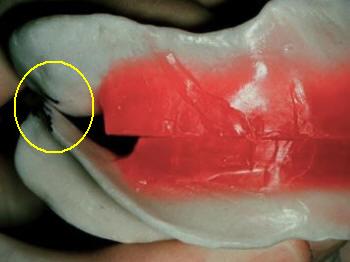

5-Determinar la relación maxilo-facial con arco

facial anatómico y la posición de relación céntrica mandibular.

- Realice escotaduras en "V" en el rodete

inferior y superior de 3 a 5 mm de profundidad; siempre de tras de las marcas

de las guías caninas. (Ver imagen inferior)

Dígale al paciente que abra la

boca y aplique una silicona para registro

en el rodete inferior y haga morder al paciente

hasta su endurecimiento, puede guiar el

movimiento de cierre con los dedos. (Ver imagen inferior)

El

material no debe desbordar los rodetes |

Registro en céntrica

con silicona para registro |

Guíe el movimiento de cierre con los dedos. |

Demasiado material produce desbordamiento |